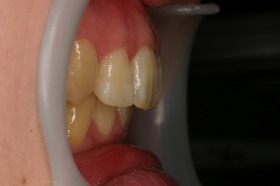

歯の矯正治療 症例ビフォー&アフター

ご覧の症例は出っ歯を矯正治療でキレイにしたケースです。

よく出っ歯は日本人に多いようなイメージがありますが

、世界的に見ても受け口と比較して出っ歯は多いようです。

このような場合では歯を抜いて矯正するか

、抜かずに矯正するか分かれるケースです。

ご覧の矯正歯科治療の場合は、抜いて矯正歯科

治療していますが東京世田谷矯正歯科センターでは

非抜歯矯正歯科治療をベースにしています。

どうしても抜かないとキレイにならない場合のみ

抜歯して矯正歯科治療しています。